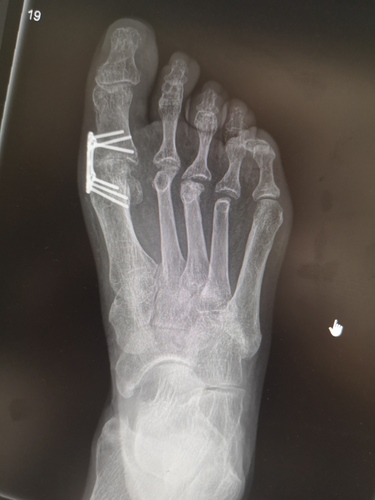

Nowa metoda stabilizacji w usztywnieniu pierwszego stawu śródstopno-paliczkowego